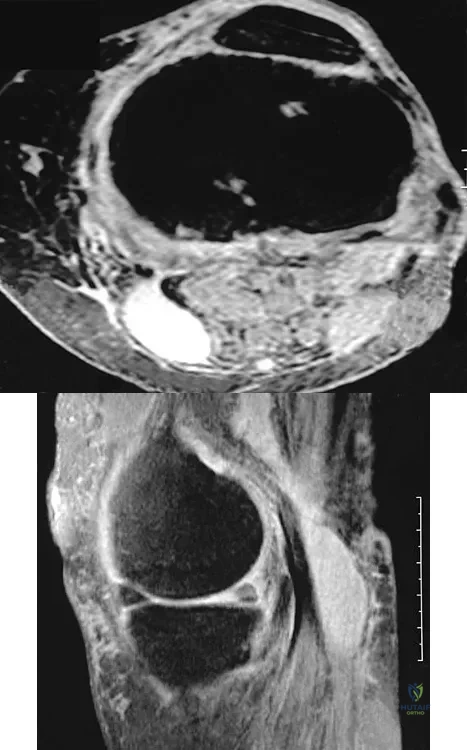

Question 31High Yield

A 23-year-old woman reports right knee pain and fullness. The pain is worse with activity but also present at rest. Radiographs are shown in Figures 20a and 20b. What is the most likely diagnosis?

Explanation

Question 32

An 80-year-old woman notes a painless mass posterior to her left knee. MRI scans are shown in Figures 31a and 31b. What is the best course of action?

Explanation